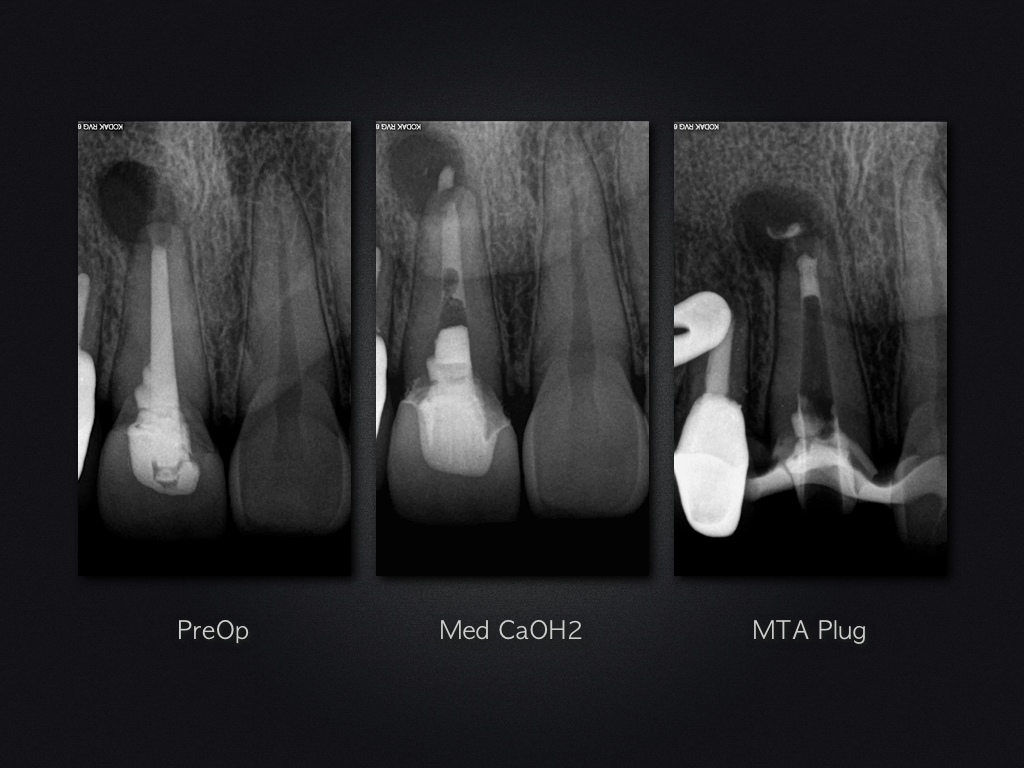

Und es heilt doch!